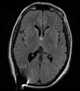

Colloid cyst of third ventricle

A colloid cyst is a non-cancerous tumor in the brain. It consists of a gelatinous material contained within a membrane of epithelial tissue. [Source: Wikipedia ]